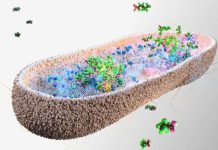

The sensor is designed to work by detecting a particular type of small protein, a cytokine known as Tumour Necrosis Factor alpha (TNF alpha), that is involved with inflammation in the body.

According to research, abnormal cytokine levels have been linked to a wide variety of diseases, including Alzheimer’s disease, cancers, heart disease, autoimmune and cardiovascular disease.

TNF alpha has the ability to act as a biomarker and a measurable characteristic that can indicate health status.

COVID-19 can also cause inflammatory reactions known as ‘cytokine storms,’ and studies have shown that cytokine inhibitors are an effective treatment for improving chances of survival.